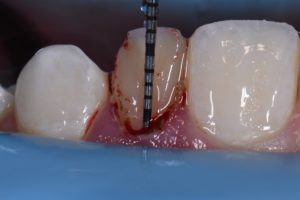

This case was referred to me for improvement of the esthetics of composite bonding on #7 and 10. A diagnostic wax-up was generated as the referring dentist required certain proportions relative to primary anatomy to be confirmed before starting. A decision was made to modify the gingival contour of 10 (diode, 810nm, 980nm, 1.0W SuperPulsed) (Gemini, Ultradent, UT), with bone sounding the basis for whether osseous recontouring was necessary. In this case, transsulcular osseous recontouring using a Wedelstaedt chisel (Kois) (Brasseler) was utilized to re-establish biologic width on the day of the restorations. Approximate full healing time: 3 months. Approximate “purple” look to gingiva: 2-3 weeks. Most of the old composite was removed except for areas where it could not easily be distinguished from tooth structure. After defining finish lines, the teeth were isolated with metal strips and micro air abraded (27 micron aluminum oxide) before a total etch approach. Silane coupling agent was utilized (GC G-MultiPrimer) before bonding (GC G-Premio Bond). A layered approach was utilized (4 separate layers) using shades XL1 Enamel, A1 Enamel, XL2 Dentin, Trans Clear from Kerr Harmonize.